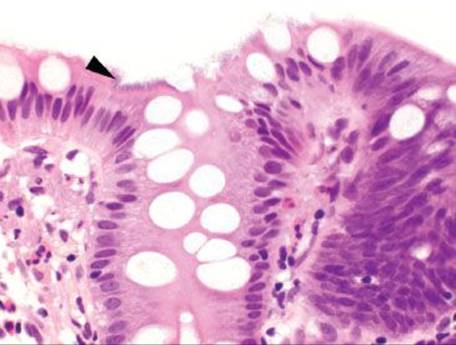

Figure 4.273 Endometriosis. Higher power of previous image. Cilia are not definitively identified in this suboptimal specimen. Biopsies of the lesion had raised concerns for an infiltrating adenocarcinoma because the glandular elements were not recognized as endometrial, the overlying reactive changes were interpreted as dysplasia, and numerous mitotic figures were seen.

Endometriosis is the presence of at least two of the three following features outside of the uterus: endometrial glands, stroma, and hemorrhage (Figs. 4.271–4.273). Up to 37% of women with endometriosis have intestinal involvement, and any layer of the bowel can be involved. The clinicopathologic presentation is diverse and presentations can overlap with appendicitis, IBD, diverticular disease, infectious colitis, a surgical acute abdomen, malignancy.125–128 Endometriosis involving the rectum commonly presents as bloody diarrhea. Associated pathologic findings can include strictures, ulceration, fissures, ischemia, and intussusception.125 The lesions can appear as polyps or bleeding mass lesions, raising clinical concerns for malignancy. The overlying colonic epithelium can be markedly reactive and mimic dysplasia, leading to the misdiagnosis of colonic adenocarcinoma. Occasionally, only the stromal component is seen and a diagnosis of sarcoma is entertained. In these cases, usually the endometrial glands can be identified on deeper sections. Confirmatory immunohistochemical stains include ER and PR to highlight the glandular components and CD10 to highlight the endometrial stroma.

Figure 4.274 Endometriosis (ER immunostain). An ER immunostain shows diffuse nuclear reactivity in the indicated cells and a CD10 highlighted the stromal component (not shown), supporting the revised diagnosis of endometriosis. We have seen similar cases raise concerns for spindle cell sarcomas when the glandular elements were not present. Deeper sections and ancillary ER, PR, and CD10 are helpful diagnostic tools in challenging cases. Always consider endometriosis in a reproductive aged woman with a rectal mass.

Always consider endometriosis (a benign etiology) before malignancy in a reproductive aged woman with a rectal mass (Fig. 4.274).